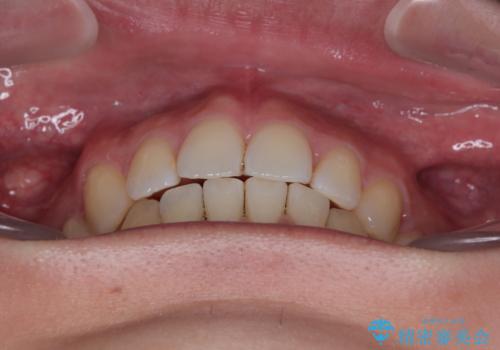

口元の突出感もなくなり満足されました。

口元が出ているのが気になる。審美装置による抜歯矯正